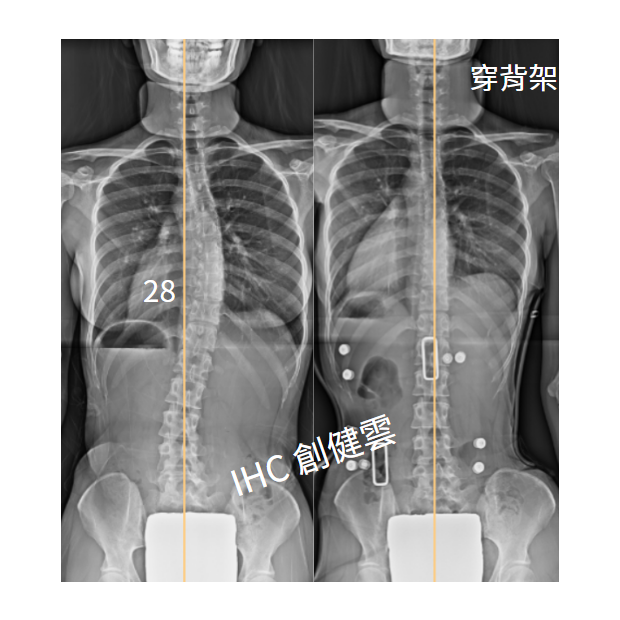

21歲成年女生,側彎28度

21歲脊椎側彎女生 胸彎28度